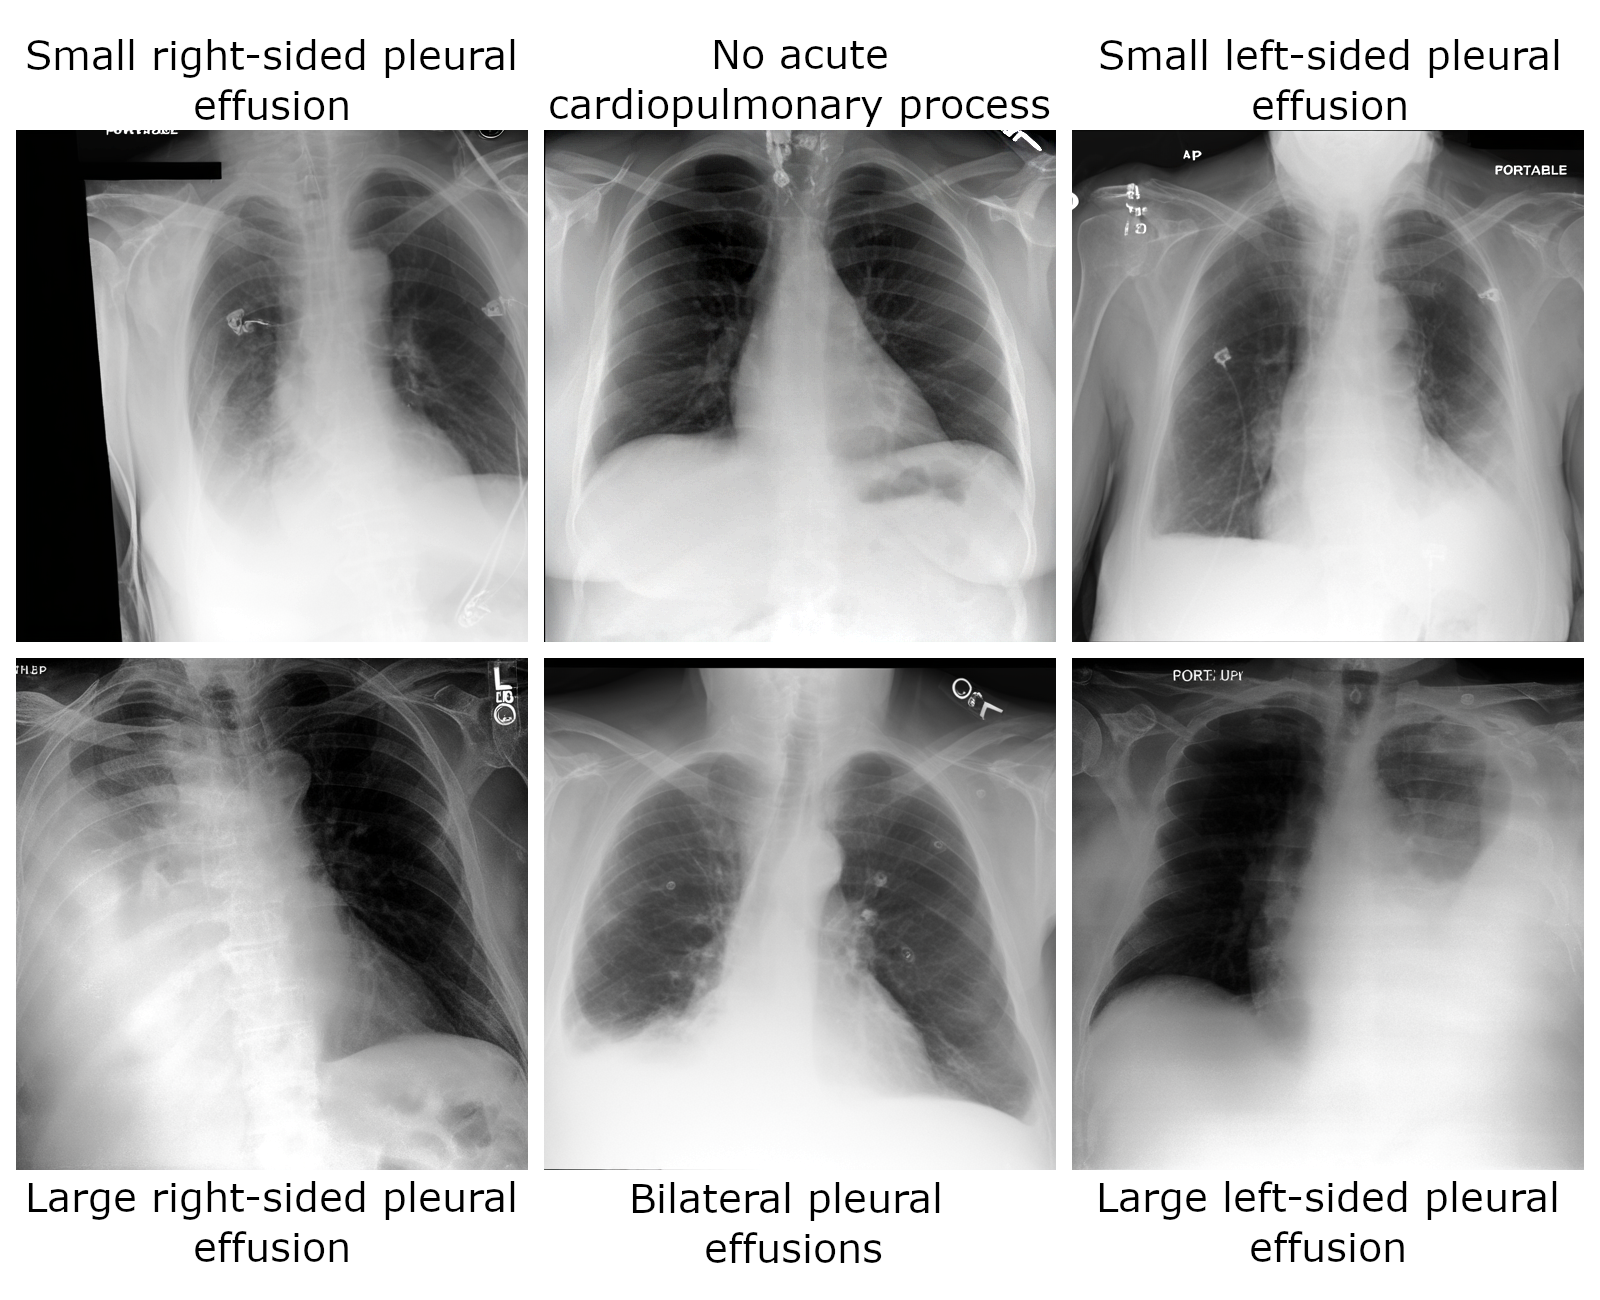

Sampling Chest X-Rays

The generation pipeline can be used to sample images via the following

import torch

prompts = [

"Small right-sided pleural effusion",

"No acute cardiopulmonary process",

"Small left-sided pleural effusion",

"Large right-sided pleural effusion",

"Bilateral pleural effusions",

"Large left-sided pleural effusion",

]

torch.manual_seed(0)

images = generation_pipeline(

prompts,

num_inference_steps=100,

guidance_scale=7.5,

).images